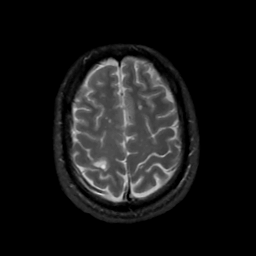

MR Study #3, February 24, 1991 -- Slice #40

[Home][Help][Clinical][Tour 1][Tour 2] Slice 40